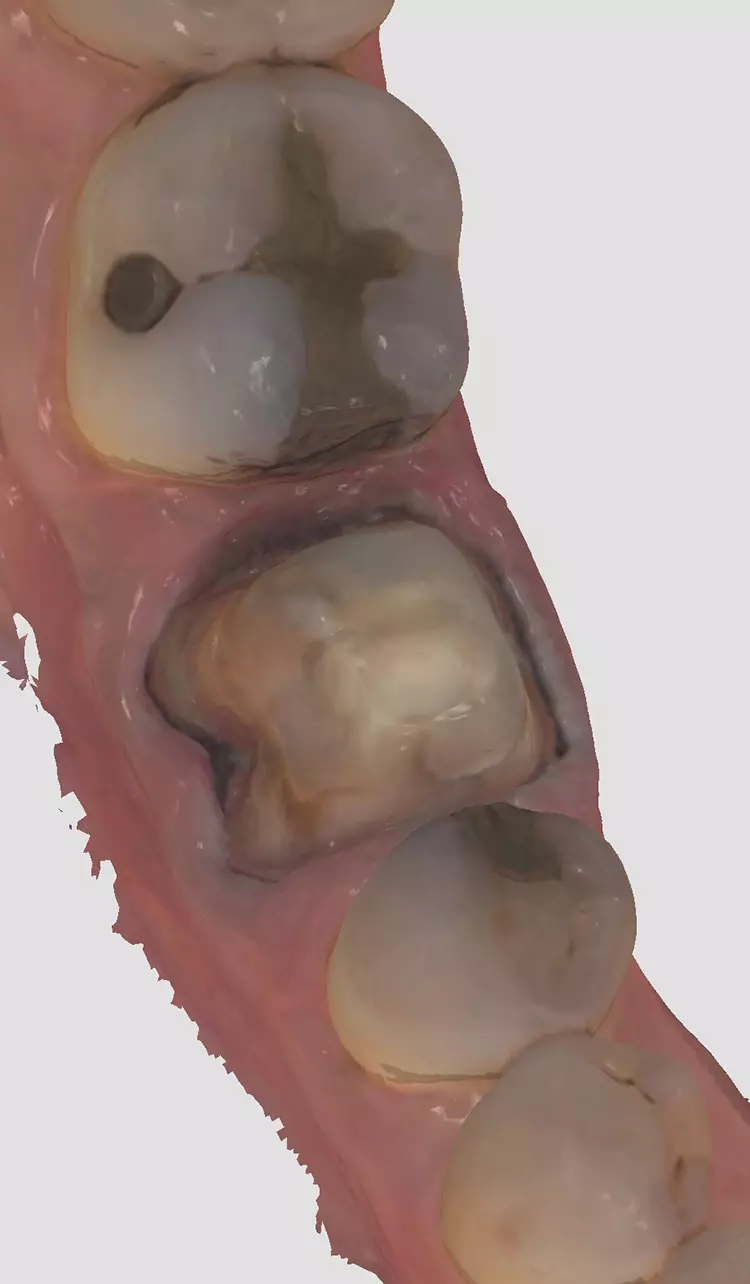

Im folgenden Patientenfall wurde eine Neuversorgung mit einer monolithischen Zirkoniumdioxidkrone im CAD/CAM-Workflow durchgeführt, nach Entfernung einer VMK-Krone, aufgrund von Sekundärkaries. Der Stumpfaufbau erfolgte effektiv und einfach mit einem Bulk-Fill-Komposit, dessen Viskosität thermisch gesteuert wird (VisCalor bulk, VOCO).

Die Behandlung begann mit dem Auftrennen und der Entfernung der Krone. Anschließend wurde die Sekundärkaries entfernt und der Stumpf mit VisCalor bulk (VOCO) repariert. Hierbei handelt es sich um ein Bulk-Fill-Komposit mit thermisch kontrollierter Viskosität, welches sich gut für Klasse-II-Restaurationen oder Stumpfrekonstruktionen eignet.

Die Präparation für die neue Krone erfolgte mit konischen Fräsern grober und mittlerer Körnung (850.014C/M, Solo Diamond). Nach der Kariesentfernung war eine Anhebung der tief liegenden Kavitätenränder erforderlich, die ebenso wie auch der Aufbau des restlichen Stumpfes mit VisCalor bulk (VOCO) erfolgte. Um eine Weichgewebskonditionierung zu ermöglichen, wurde eine provisorische Krone hergestellt, die der Patient vor der digitalen Abformung einige Wochen getragen hat (Abb. 2a und 2b).